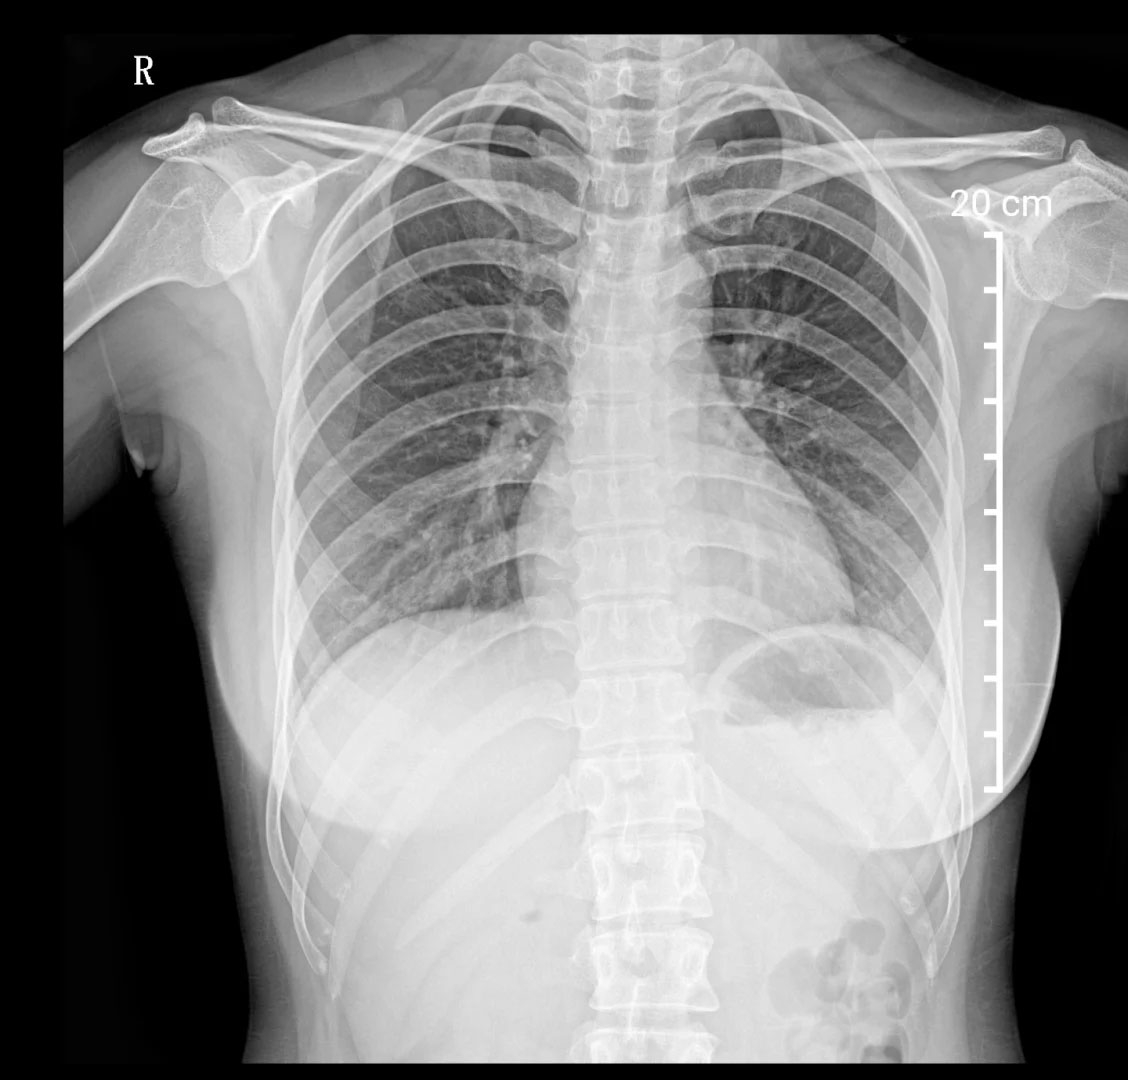

胸部X光檢查,建筑工地的環(huán)境復(fù)雜,肺部檢查很重要。有的工種需要長期接觸灰塵,可能會引起輕微肺部炎癥。在工地工作的時候,盡量要佩戴好口罩。

胸部X光檢查.jpg